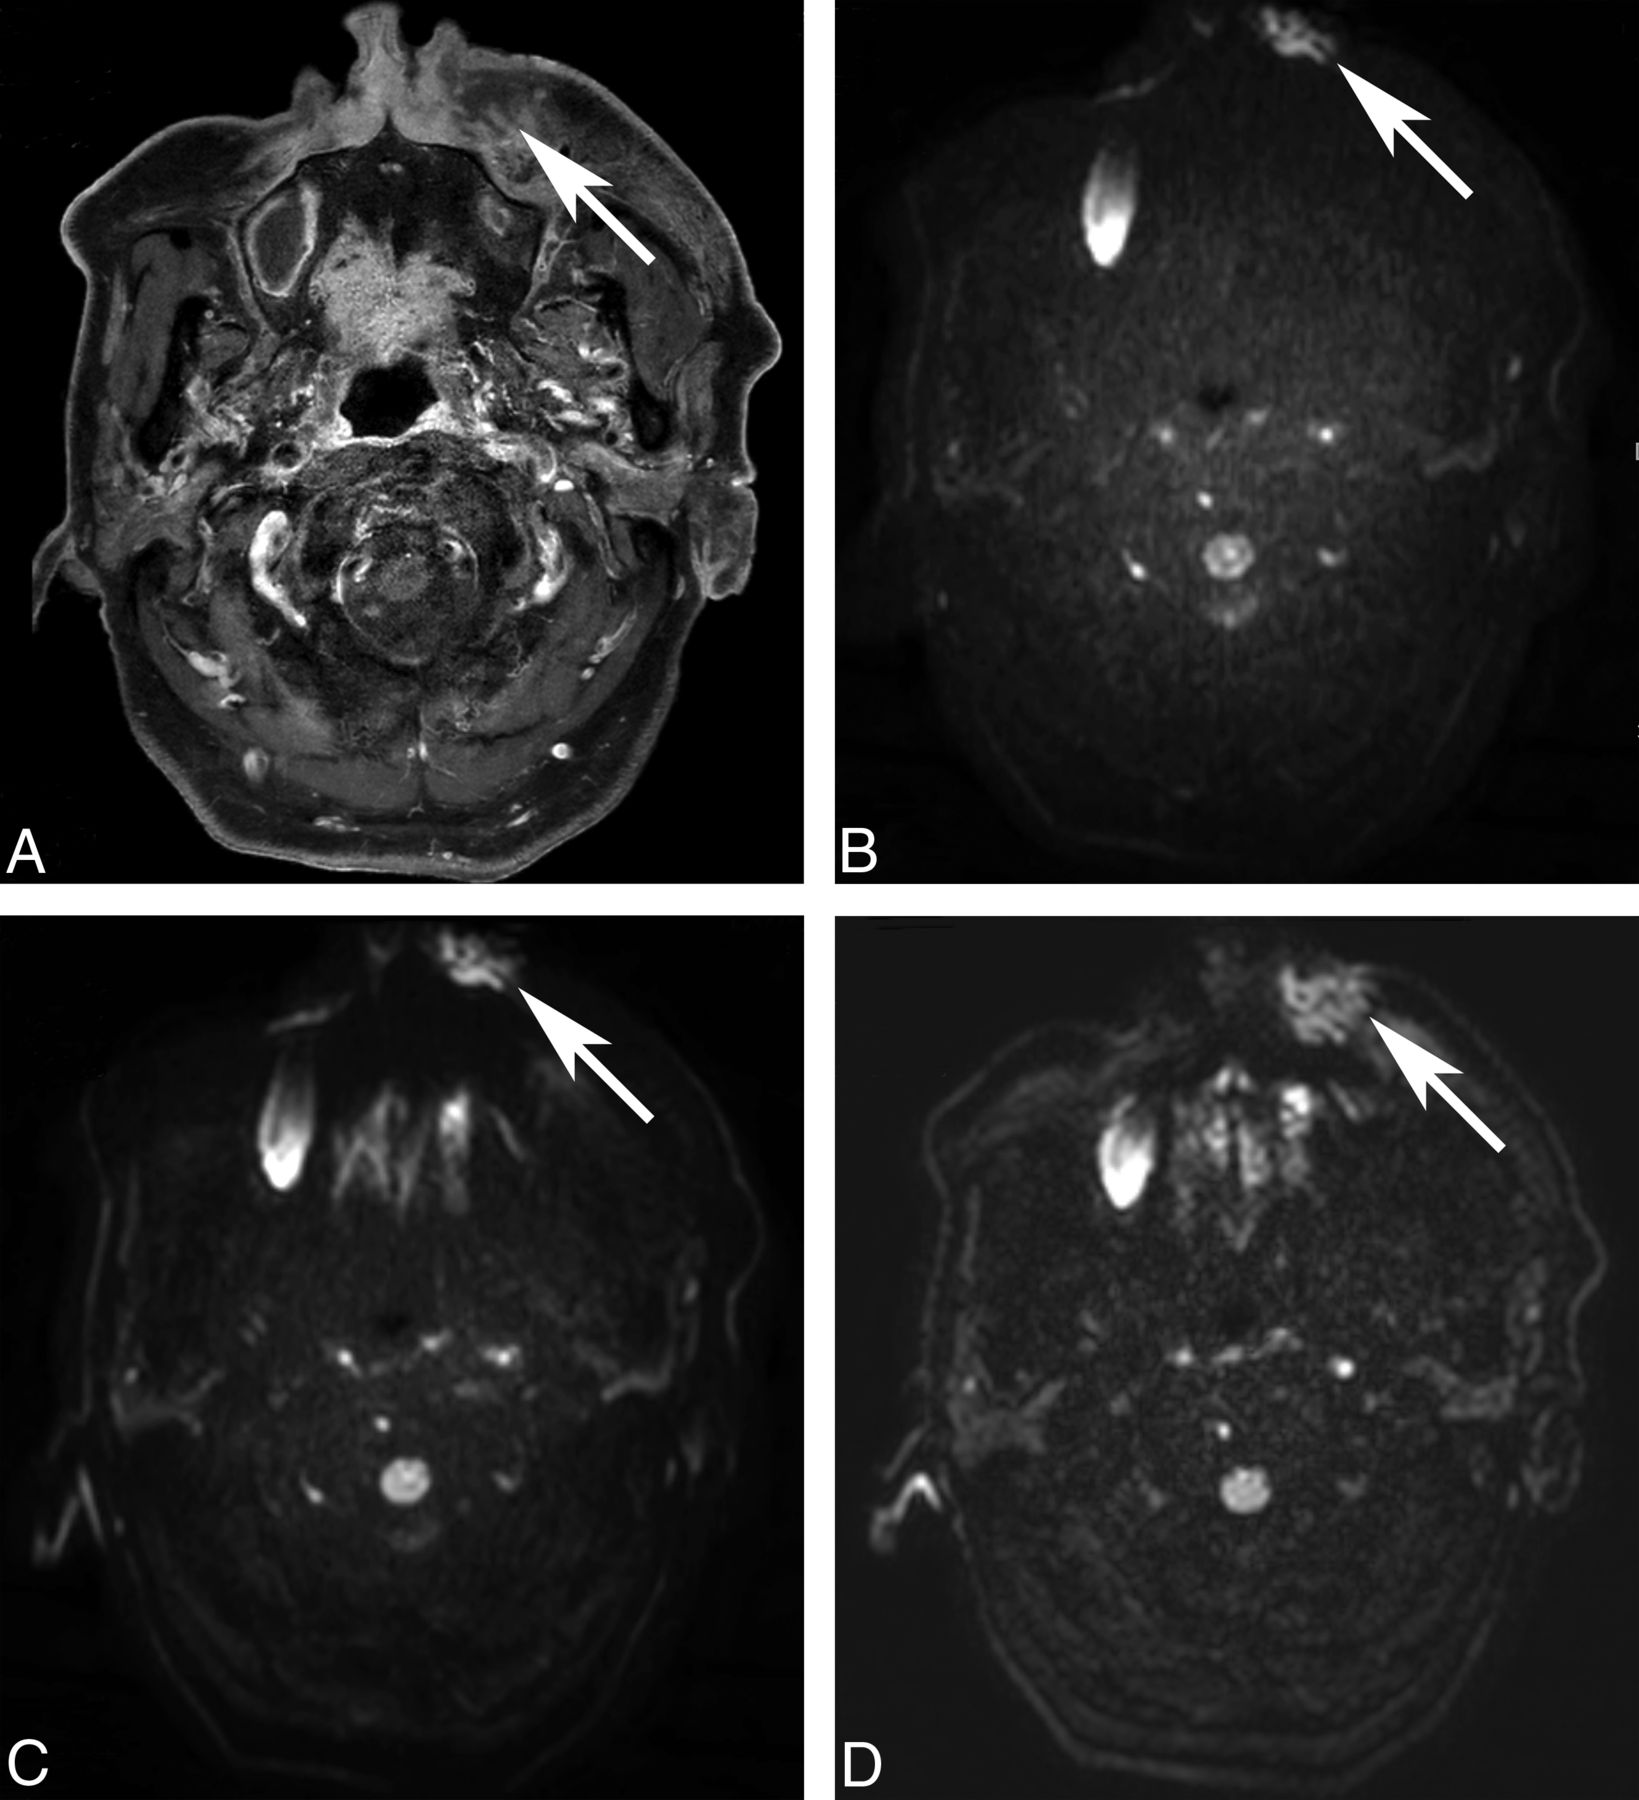

Image distortion of DWI. An 85-year-old man underwent MR imaging for the evaluation of a left premaxillary abscess (A, post-contrast-enhanced T1WI, arrow). Image distortion is increased on ssEPI-STIR (B, arrow) and ssEPI-SPIR (C, arrow) and decreased on msEPI-SPIR (D, arrow). The left premaxillary abscess is not distorted by the susceptibility artifacts only on msEPI-SPIR.

On-line Table 5 summarizes visual scores for image distortion. Mean visual scores for image distortion were significantly higher in msEPI-SPIR than in ssEPI-STIR and ssEPI-SPIR (both readers, all regions, P < .001) (Fig 2). The mean scores between ssEPI-STIR and ssEPI-SPIR showed no significant differences for both readers (all, P > .05).

Our results of the qualitative imaging assessment showed that fat suppression was more homogeneous in ssEPI-STIR than in msEPI-SPIR and ssEPI-SPIR (On-line Table 4). This result agrees with previous studies, which reported that STIR could provide more homogeneous fat suppression in body parts with severe field inhomogeneity than SPIR.4,10⇓–12,19 With the same use of SPIR, msEPI-SPIR had a higher visual score for fat-suppression uniformity than ssEPI-SPIR in the buccal and mental regions. We believe that this result was due to the reduction of ghost artifacts from unsuppressed fat signals on the msEPI sequence compared with the ssEPI sequence (Fig 1).5,15⇓–17 Unlike ssEPI-SPIR, the reduction of ghost artifacts could eliminate the obscuring of targeted structures by unsuppressed fat signals on msEPI-SPIR. The difference between msEPI-SPIR and ssEPI-SPIR was not significant in the orbital region and posterior neck where fat suppression was equally excellent and in the shoulder where both sequences failed in homogeneous fat suppression. In the orbital region, all 3 sequences showed comparably excellent fat-suppression homogeneity. More important, regarding image distortion, the distortion was much more reduced in msEPI-SPIR than in ssEPI-STIR and ssEPI-SPIR (On-line Table 5 and Fig 2). Taken together with the above results, we concluded through visual assessment that msEPI-SPIR provided the best image quality with relatively homogeneous fat suppression and less image distortion compared with ssEPI-STIR and ssEPI-SPIR, but for imaging the shoulder region, msEPI-SPIR could be more limited than ssEPI-STIR.